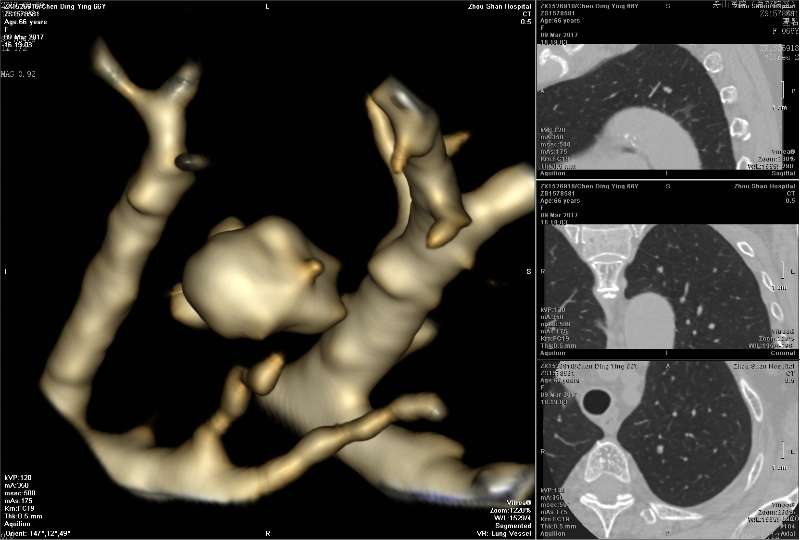

有时曲霉菌团局部CT值很高,那大多是锰化 ABPA的粘液栓高密度,据说是草酸钙,我觉得也可能是锰化(待证实)

3rd 在隔离肺的支气管里 也是在扩张的支气管内,有炎症细胞 紫红的可能是锰铁化,曲霉菌能吸收空气中的锰铁元素,在周边